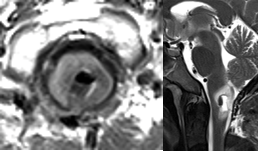

36 岁男性,主诉左侧全身感觉障碍 4 个月,伴轻度偏侧肢体无力。MRI显示延髓下部有一几乎无强化、信号均匀、占位性病变,并向下延伸累及颈髓。患者同意手术,目标为最大限度减瘤并获取确切组织病理学诊断。

术前MRI

幸运的是,手术效果非常好,未出现新的神经功能障碍。组织病理学证实为高级别胶质瘤,WHO III 级,未检出 H3F3A 或 IDH1 突变;无 1p/19q 联合缺失,p53 蛋白无高表达,O6-甲基鸟嘌呤-DNA 甲基转移酶(MGMT)启动子未甲基化。

术后MRI

术后患者接受局部放疗联合替莫唑胺化疗。术后 1 年未见肿瘤进展,生活自理。巴教授对他进行了几年的随访。经过放射治疗和靶向化疗后,他的状况仍然很好。